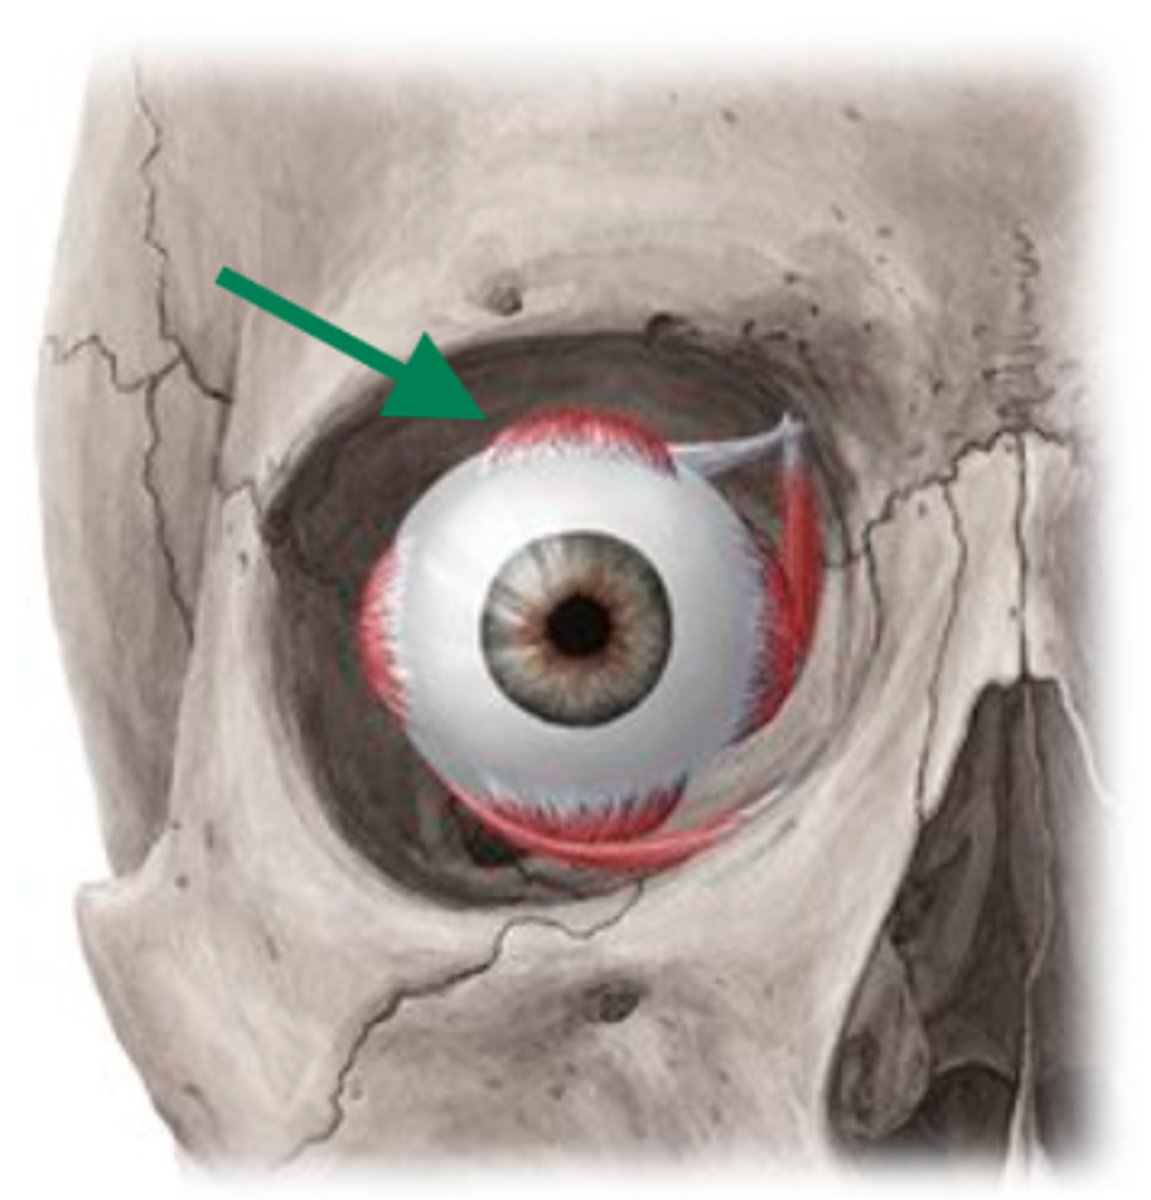

levator palpebrae superioris

superior rectus

lateral rectus

superior oblique

superior oblique

superior rectus